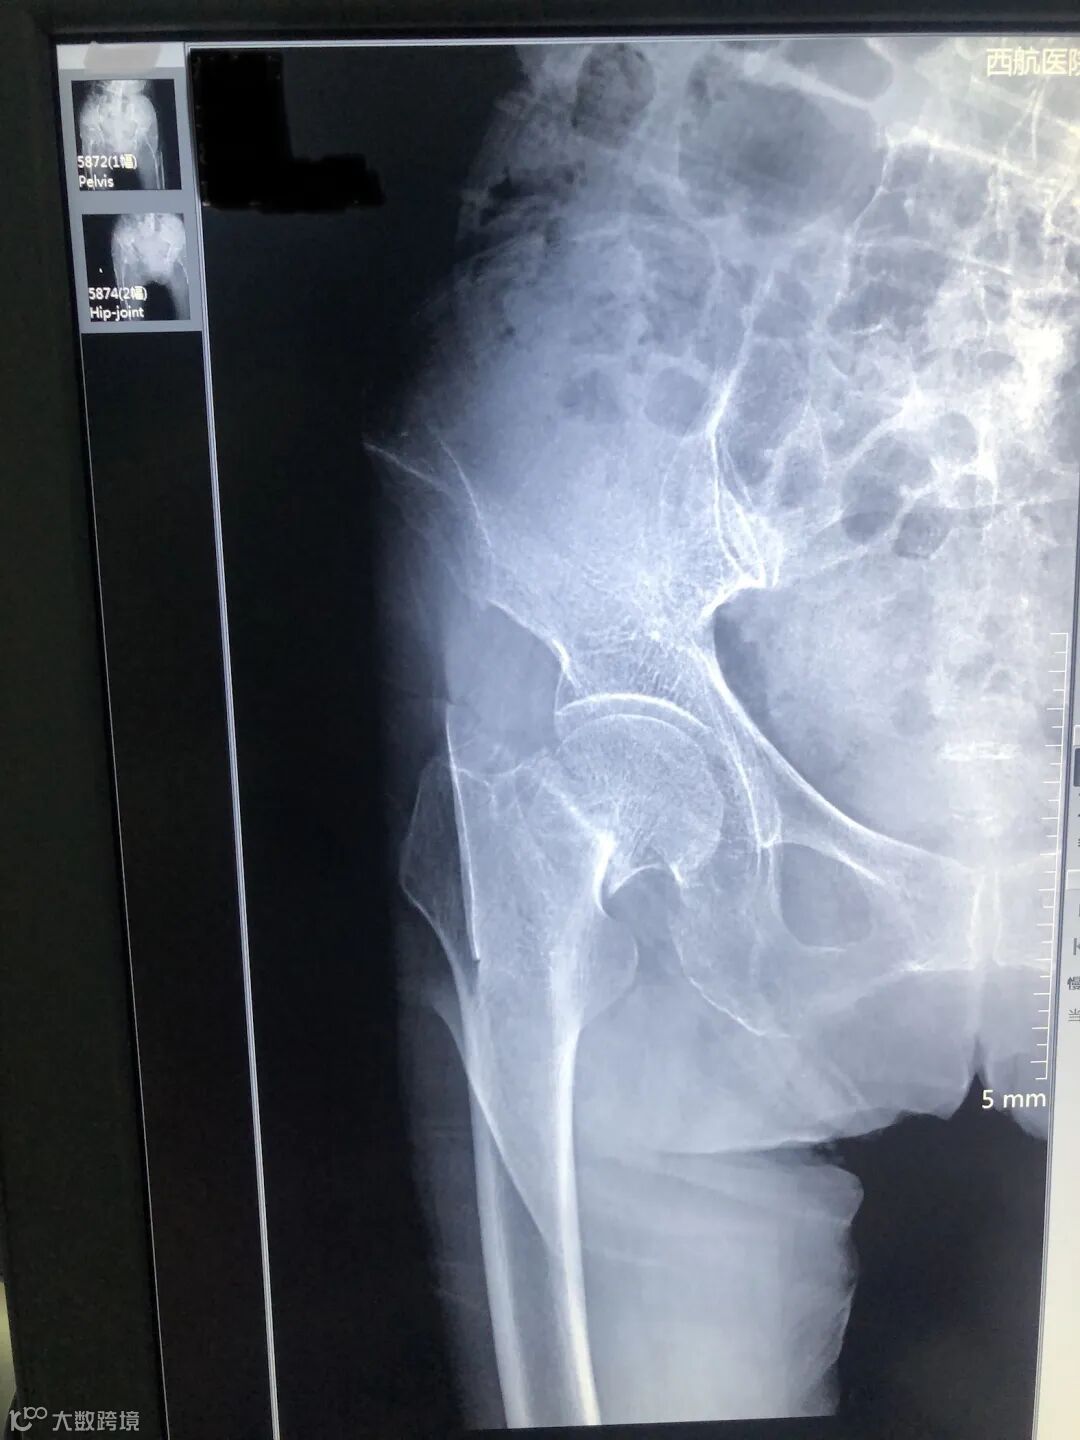

2月10日,疫情高峰,一位88岁高龄老太太,在家中不慎跌倒致右髋关节疼痛难忍,活动障碍,因疫情原因不敢来医院就诊,在家中卧床强忍2天,实在难以忍受来到我院。经过严格的流行病学及相关检查,发现右侧股骨颈骨折,新冠专家组排除新冠肺炎后收住外科,患者高龄,基础病多,如不手术,长期卧床死亡率极高,本着痛苦小、恢复快,早下地的理念,外科团队在入院第二天成功就实施了右侧人工髋关节置换术,手术前后只用1个小时,术后第一天便能坐起,第二天就开始下地活动,极大的减少了患者卧床痛苦和并发症。在我科医护人员的精心治疗下,目前老人已拆线顺利出院,出院时老人及家属连连道谢,感谢外科医护人员的细心照料,感谢技艺精湛的医护们挽救了她的生命,看着老人一家欢天喜地的回家,最开心的是每一名医护人员。

术前X片